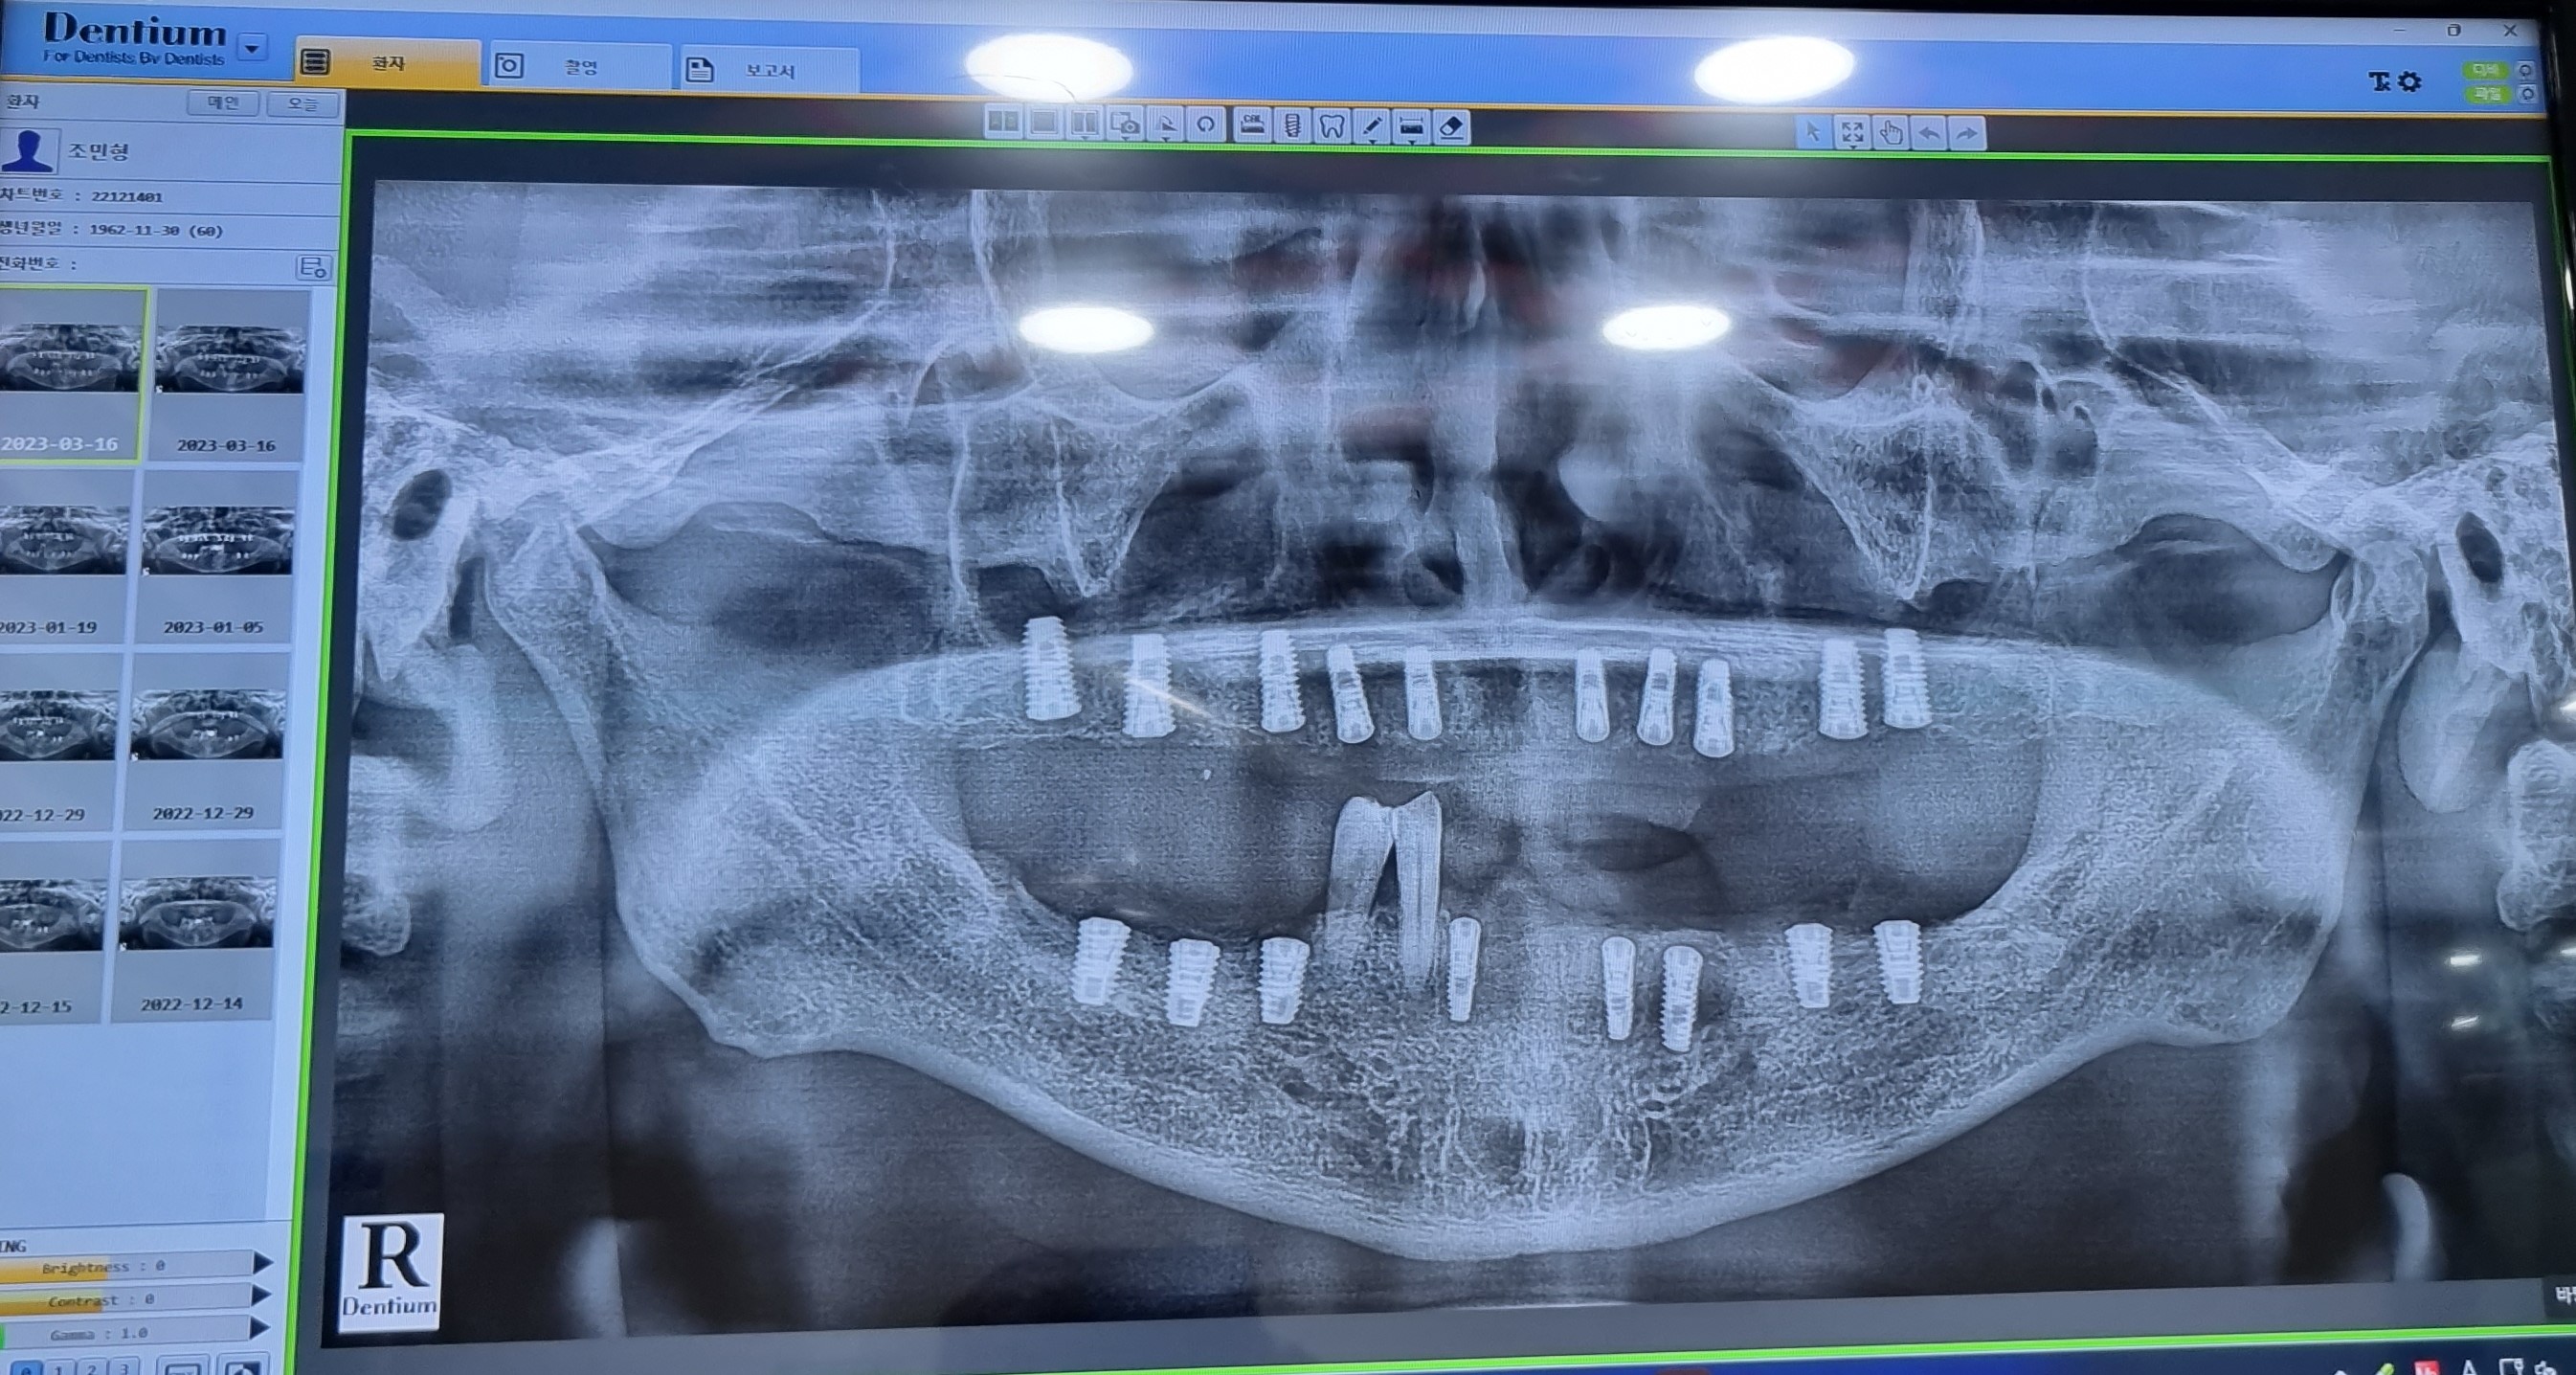

2022 1229

1차 윗니 상악上顎동 거상술

오늘은 윗니上顎 우축 14.16.17 치조골이식술을  동반한  인공치아  식립植粒술이 진행하였습니다.

잇몸을  절개하여  임몸뼈에  임플란트dental implant의  뿌리  부분인  픽스쳐Fixture를

식립植粒하는  수술입니다.

이제  윗니上顎 10X-ray 이미지에서도 모두 1차  수술  치료가  깔끔하게  긑낫습니다.

자연 치아의 뿌리처럼 잇몸뼈가 단단히  붙어야  흔들리지  않고   사용할  수 있기  때문에  뼈가

단단히  붙도록  하기  위해서는  상학上顎 6개월정도  기다려야  합니다